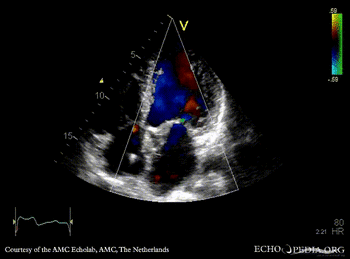

E00844.gif E00845.gif

PLAX: abscess of aortic valve prosthesis PLAX with Color Doppler: severe mitral regurgitation